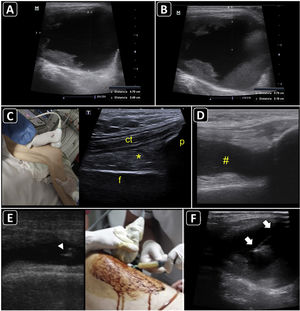

PreprocedureWith a linear probe (or a convex probe in obese or edematous patients), ultrasound aids in differentiating subcutaneous tissue edema, soft-tissue fluid collections (e.g., abscesses), periarticular disease (e.g., bursitis), or an intra-articular effusion.

In transverse and longitudinal views, soft-tissue fluid collections are measured, as well as the distance to the skin, to estimate the needle depth of insertion and to choose an adequate needle length (Fig. 5A,B). Color Doppler aids in defining the presence of vascular structures near the lesion, to avoid puncturing when inserting the needle.

Ultrasound-guided aspiration of soft tissue collections and arthrocentesis. A) Soft tissue fluid collection is identified and measured. B) Distances are measured to estimate the needle depth of insertion and length to be used. C) Technique for finding the suprapatellar articular recess of the knee and its corresponding ultrasound images; p, patella; t, cuadriceps tendon; f, femur; asterisk, fat pad (articular recess). D) Knee effusion is indicated by the symbol #. E) Real-time ultrasound-guided arthrocentesis of the knee, obtaining a purulent fluid. The arrowhead indicates the bevel of the needle that reached the articular effusion. F) Real-time ultrasound-guided aspiration of soft tissue collection. The needle is indicated by arrows.

Ultrasound anatomy of each joint should be well known for assessing effusion. Given its frequency and ease of access, knee ultrasound is reviewed herein. With the linear probe placed longitudinally above the patella and the probe marker pointing cephalad, the superior portion of the patella, quadriceps femoris tendon (long axis), fat pad, and femur should be observed (Fig. 5C). The effusion will be located below the quadriceps tendon and above the femur (Fig. 5D). Once fluid effusion is recognized, the probe is rotated 90 degrees into a transverse view so that the probe marker faces to the patient's right side. The distance from the skin to the effusion is then measured to estimate the needle depth of insertion and length to be used.

ProcedureReal-time technique is used to aspirate soft-tissue collections and perform arthrocentesis. The out-of-plane and in-plane approaches are selected on a case-by-case basis. For example, aspiration of abscess and knee arthrocentesis are best performed using the in-plane approach (Fig. 5E and 5F), whereas the out-of-plane approach is preferred for aspiration of effusion from the wrist joint. A fully sterile barrier technique is required to do so.